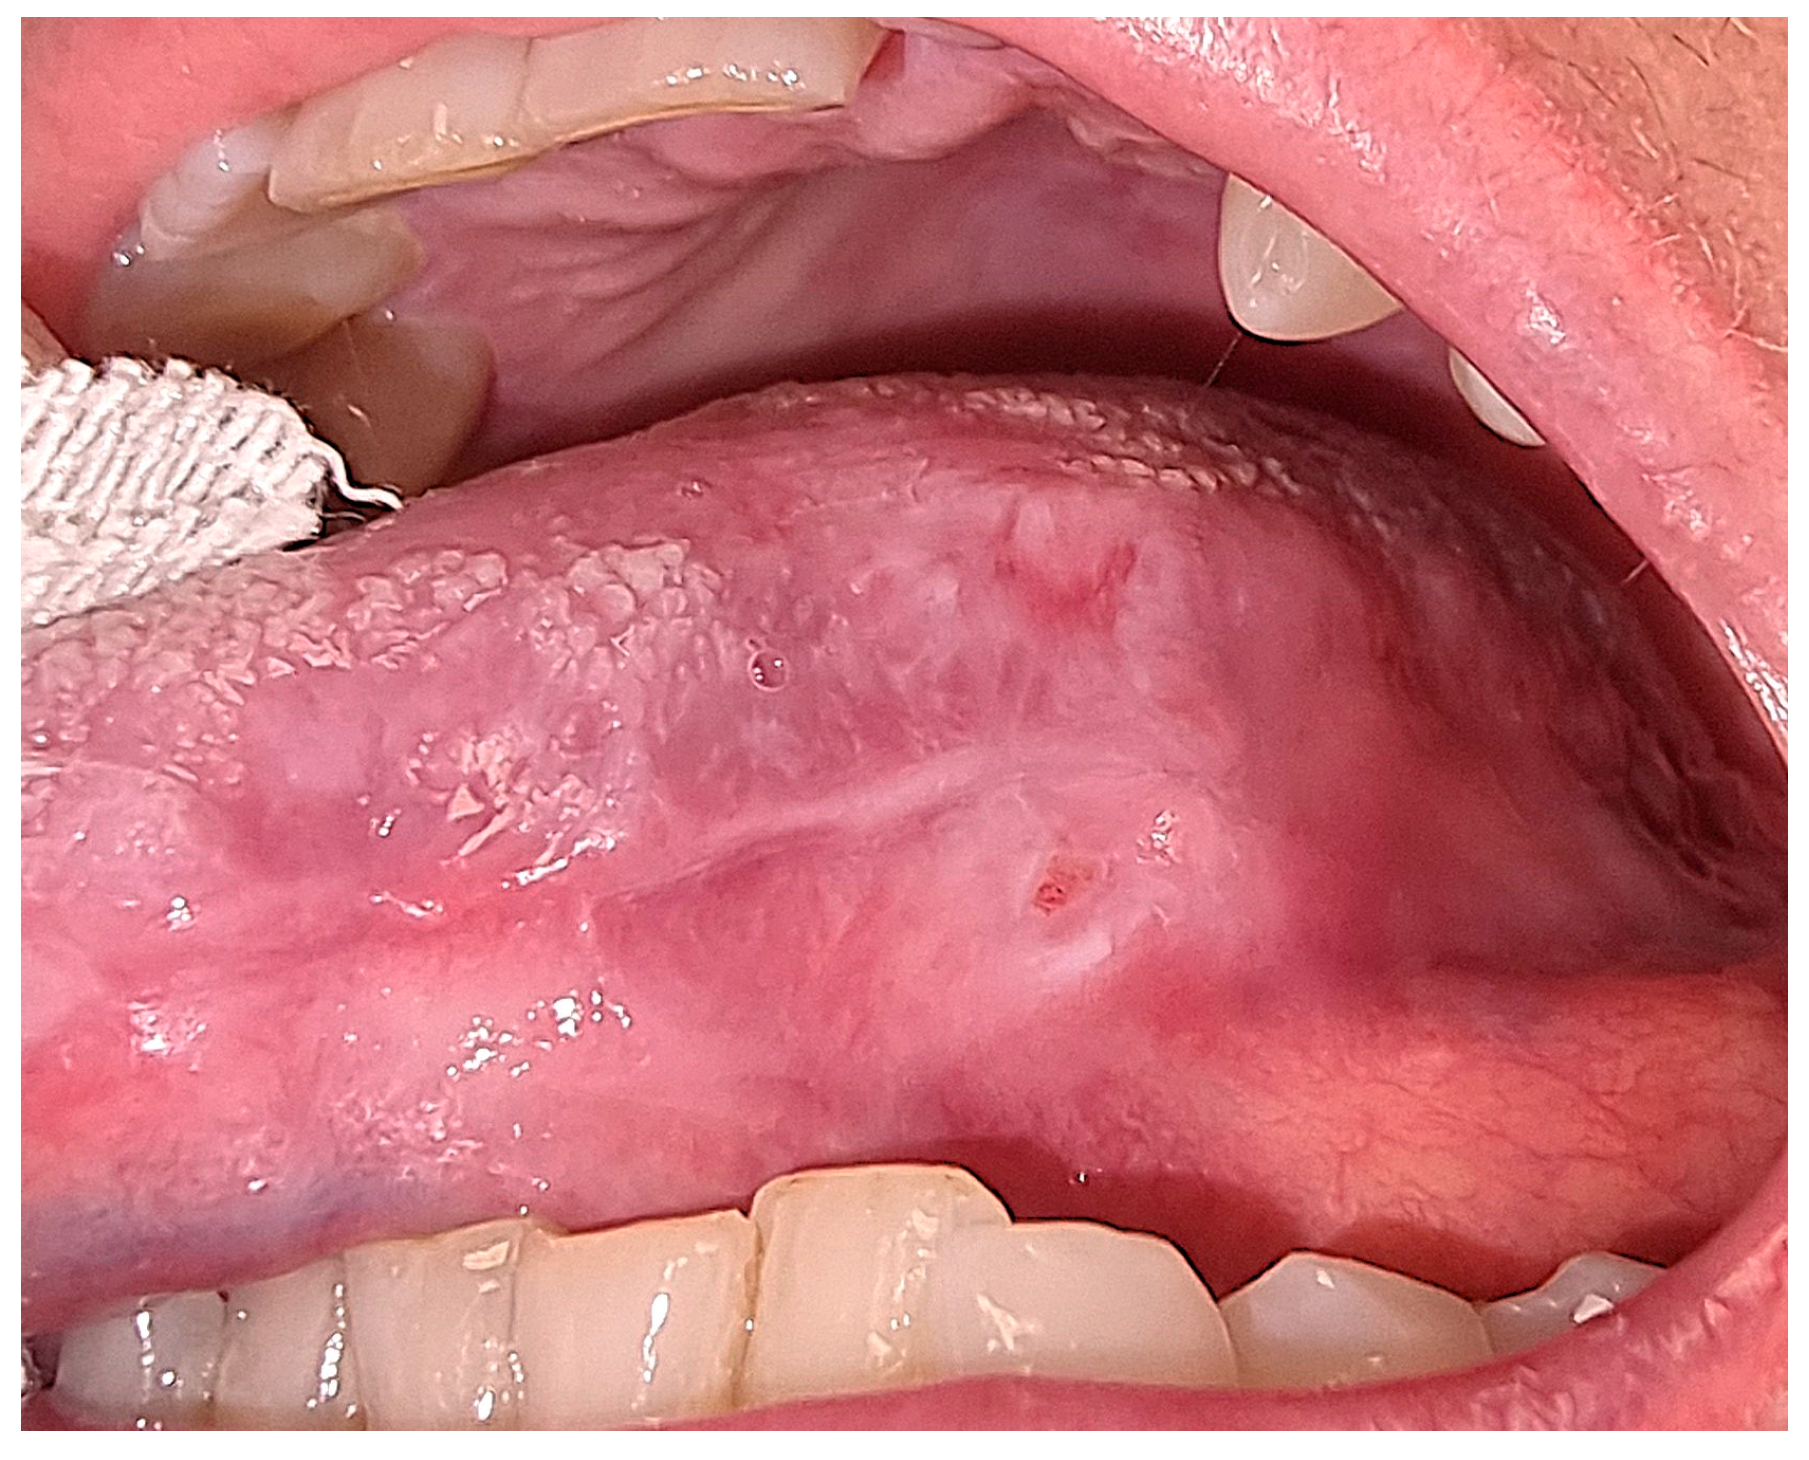

Case Treatment

3. Results